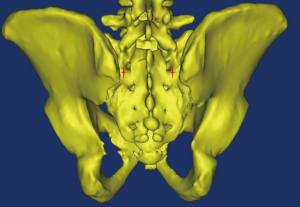

The optimal entry point of S2AI screw is located approximately 1 mm inferior and 1 mm lateral to the S1 dorsal foramen (11) (Figure 2), which is more medial and lower profile than iliac screw fixation. After determining the screw entry point, a drill or probe is used to fashion the screw trajectory (Figure 3), which can vary among individuals. Pre-operative screw trajectory measurements and intra-operative imaging may help optimize screw trajectory.